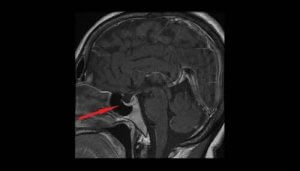

診断の確認に役立つ最も関連性の高いテストは、視野の検査とCTおよび脳のMRIです。